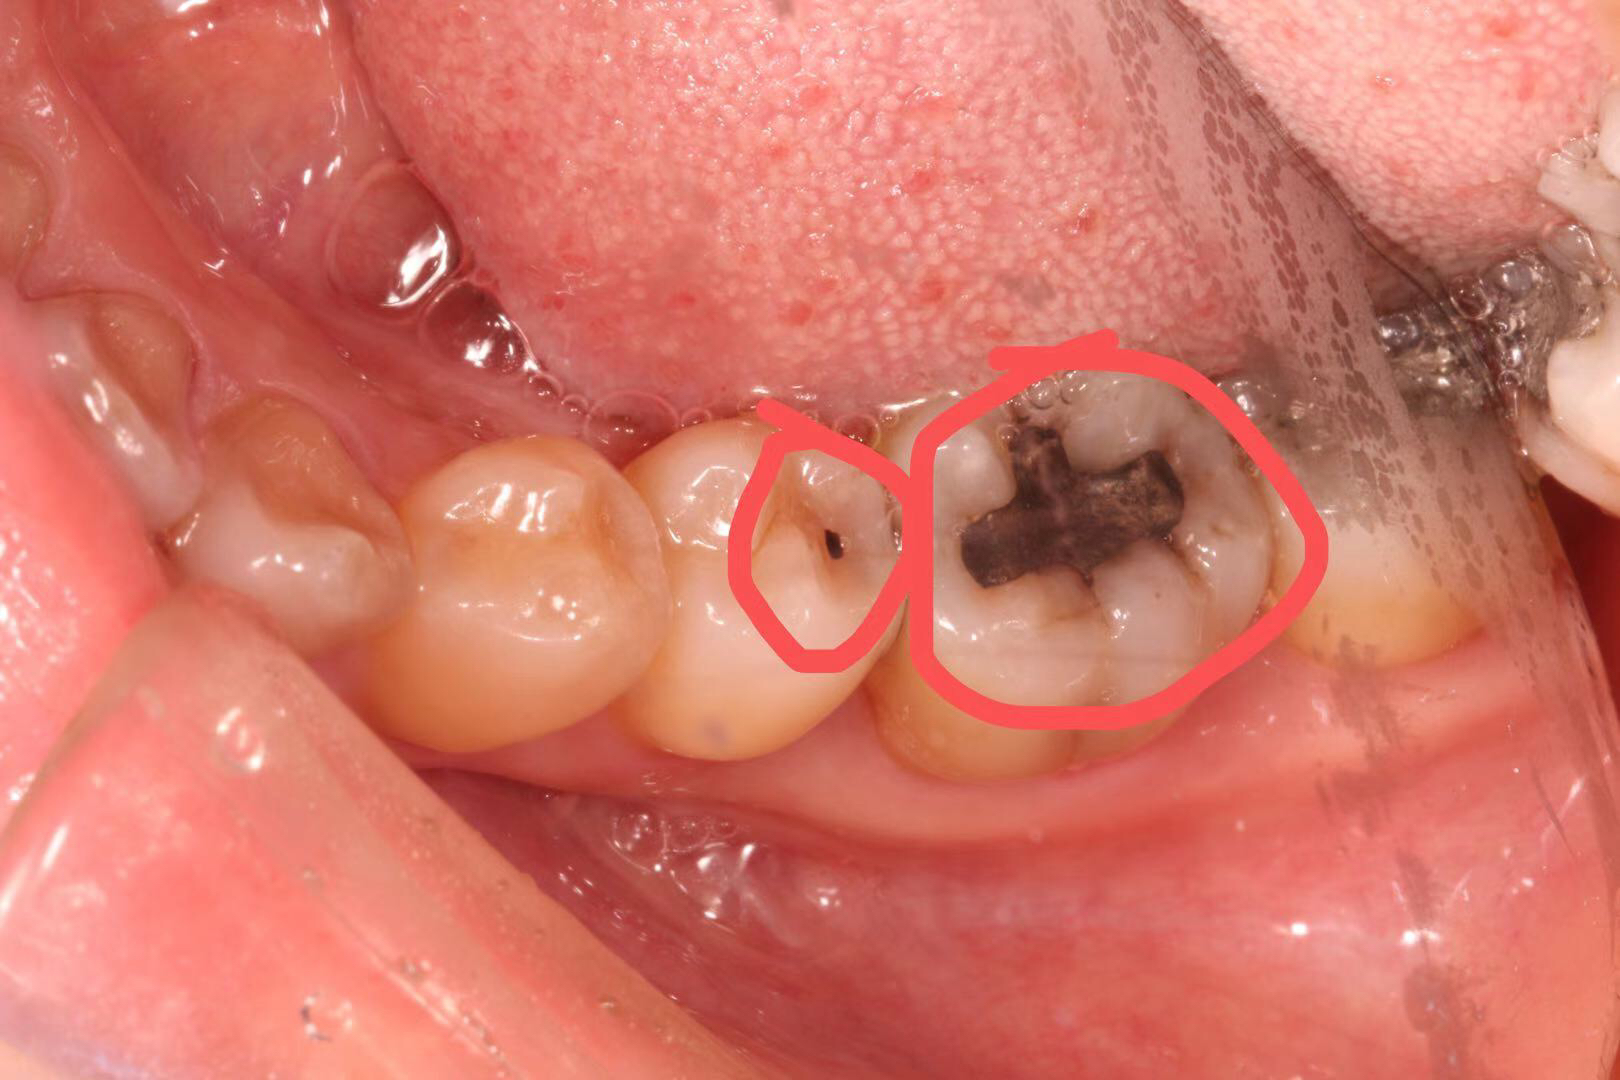

患者多年前银汞充填,因边缘微渗漏导致继发龋坏,我院采用相较于传统补牙更耐用、美观、可承受更大咬合力的修复方式:嵌体修复。

治疗步骤:1 去净龋坏, 2 制备洞形,3 扫描,4 切割制作,5 戴牙。